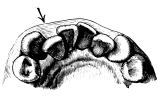

The value of splitting roots in a case similar to that shown in fig. 33 is apparent, for, as will be seen, it allows each root to be removed in the line of its inclination.

a b

Fig. 33.

(a) Lower molar with divergent roots. (b) The dotted lines show the direction in which the root can be removed if the tooth is divided as suggested in the text.